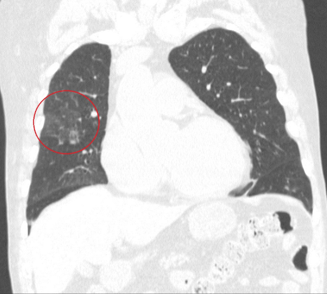

Пятно в легком что это может быть